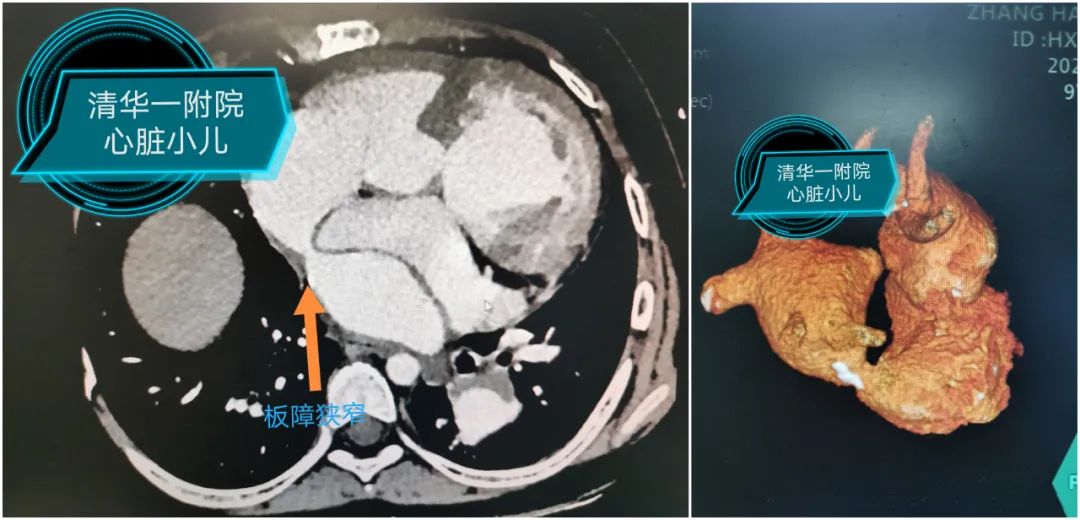

术前CT提示:肺静脉板障梗阻最窄处仅5mm;超声提示:板障入口处血流速度加快,最大前向血流速度为1.8m/s。

手术选择在杂交手术室进行,在几乎没有明显出血的情况下,靳永强顺利游离肺组织,显露左侧心房。在食道超声的引导下准确选择心房穿刺部位,使穿刺部位在板障狭窄的正下方,顺利将球囊支架系统通过狭窄部位;采用食道超声及X线下确定支架植入部位,操作如行云流水般一次性扩张成功,食道超声及导管测量板障处血流畅通,无明显压差。患儿术后恢复顺利,3小时后撤除呼吸机,第二天便转回普通病房。回到病房的小千活动量明显好转,睡觉时终于可以平卧了。术后超声提示肺动脉压力明显降低,左心室的射血分数也恢复至正常,甚至主动脉瓣的反流也从中量降至少量。